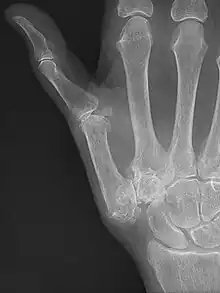

Diagnosis

TMC OA is diagnosed based on symptoms and signs.[8] Radiographs can confirm the diagnosis and the severity of TMC OA. Other diagnoses in this region include scaphotrapezial trapezoid arthritis and first dorsal compartment tendinopathy (De Quervain syndrome) although these are usually easy to distinguish.

Classification

TMC OA severity was classified by Eaton and Littler which can be simplified as follows:[21][22]

Stage 1:

- slight widening of the joint space

- < 1/3 subluxation of the joint (in any projection)

Stage 2:

- Osteophytes, < 2 mm in diameter, are present. (usually adjacent to the volar or dorsal facets of the trapezium)

Stage 3:

- Osteophytes, > 2 mm in diameter, are present (usually adjacent to the volar and dorsal facets of the trapezium)

- Slight joint space narrowing

Stage 4:

- Narrow joint space

- Concomitant scaphotrapezial arthritis

A simpler classification is no arthritis, some arthritis, and severe arthritis.[23] This simpler classification system omits the potentially contradictory details of the Eaton/Littler classification and keeps scaphotrapezial arthrosis separate.